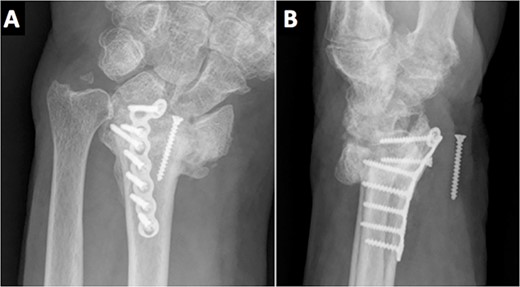

Due to the comminuted fracture and the bone osteoporosis, the final decision was closed reduction and fixation with K-wires. Due to the inadequate reduction, we decided to associate an external fixator. However, during surgery, an inadequate reduction of the ulnar column was observed, and thus, a mixed synthesis with an L-shaped plate was added (Fig. 2).